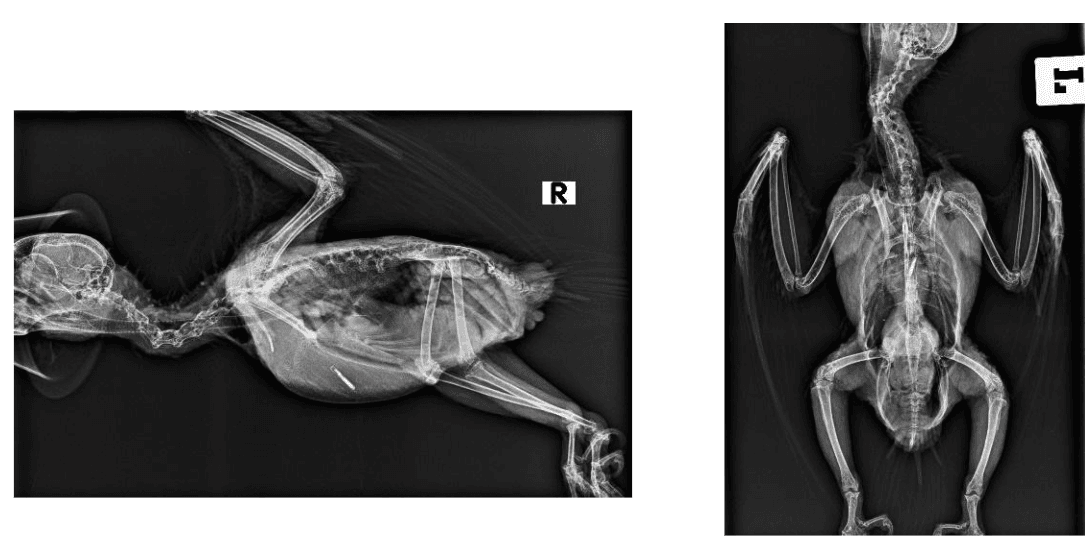

- Radiografía: para comprobar calcificaciones, tamaño del corazón o descartar otros problemas articulares.

- Radiografía: incremento en la densidad de los grandes vasos en la radiografía, calcificaciones de las arterias coronarias. Aumento cardíaco o de los vasos.